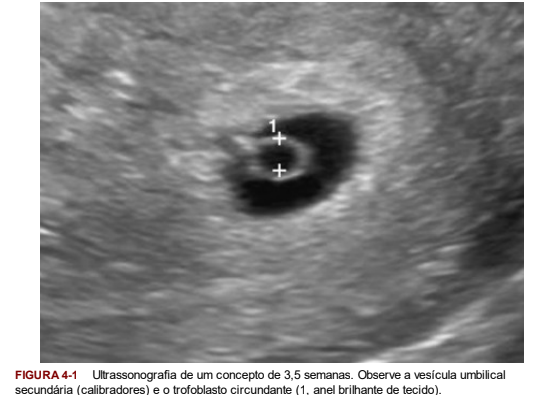

Ultrassom